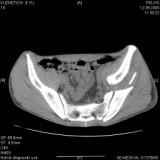

Уважаемые коллеги! Хотелось бы услышать совет по тактике лечения представлленого больного.Поступил после лечения в одном изотделений области. Травма 2,5 месяца назад. После выведенияиз шока был произведен остеосинтез перелома бедра, предплечья, до перевода к нам проводилосьвытяжение по оси шейки бедра за стержень, введенный в большой вертел. На сегодня деформацияригидна, клинически мобильности не определяется. Заранее признателен. P.S. Данный вид травм не включен в перечень "высокотехнологичных операций", направить длялечения по квотам Минздрава очень сложно.

Привет, Леонид. Оскольчатый высокий двухколонный перелом в такие сроки трогать не надо, т.к. это про такие переломы сказано: "кто с ножом на Ж. пойдет тот в ней и останется...".